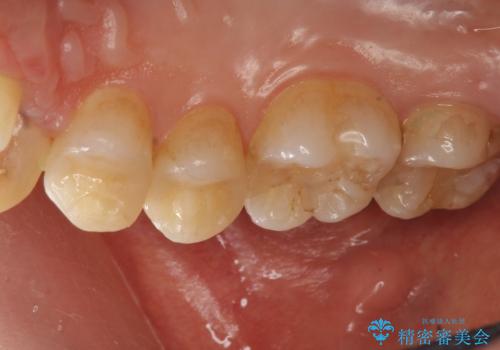

- 歯の健診にて来院。

レントゲンを撮った時にう蝕があったため、拡大鏡下でう蝕が残っていないか確認し

セラミックの詰め物(e-maxインレー)にて治療を行いました。

- e-maxインレー 7.7万円 ×2本費用は治療当時の料金となります